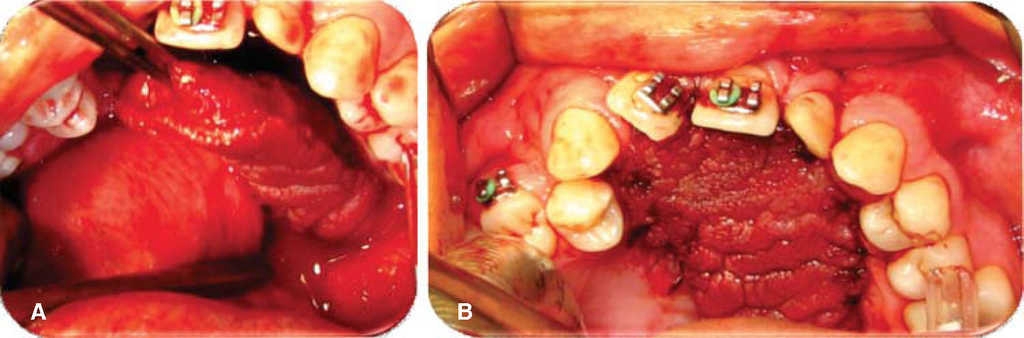

Se programa para cierre de fístula oronasal con colgajo a distancia de lengua de base anterior. Bajo anestesia general, con intubación nasotraqueal, se infiltra el paladar y el sitio donante con lidocaína con epinefrina al 2% y 1:100,000 con fines hemostáticos, se coloca un abreboca tipo Digman y se realiza una incisión perifistular con hoja de bisturí No. 15 y electro bisturí, se realiza disección de los bordes del defecto evertiéndolos y suturándolos con poliglactina 910 de 4-0, logrando un cierre del 100% del plano de la mucosa nasal, se realiza irrigación con solución fisiológica por vía nasal observado la nula salida de líquido por el defecto ya cerrado; se retira el abreboca tipo Digman y se coloca un abreboca de Mackinson, se tracciona la lengua con un punto de sutura de seda 2-0 en la punta para presentarla, se realiza un diseño de colgajo de lengua de base anterior 20% mayor al tamaño del defecto, y de una longitud aproximada de 5 cm asegurándose que cubriera la totalidad del defecto evitando la tensión; se realiza hemostasia con electro cauterio y con sutura de poliglactina 910, se realiza sutura del sitio donante en dos planos con poliglactina 910 4-0 verificando la ausencia de hematomas; se rota el colgajo de lengua sobre el defecto y se sutura con puntos simples de poliglactina 910 sobre los bordes del defecto. Se termina el acto quirúrgico sin complicaciones ni accidentes (Figuras 2,3, 4). En este caso no se colocó fijación intermaxilar, ya que por la edad del paciente se considera que es cooperador.

Figura 4 A. Rotación y eversión colgajo de lengua en lecho quirúrgico. B. Presentación de colgajo de lengua en lecho quirúrgico.